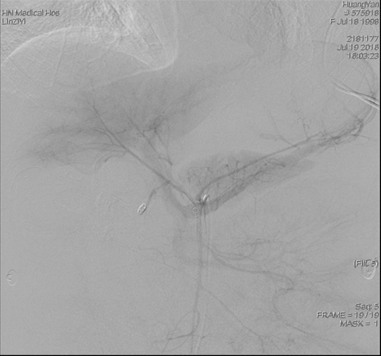

术中可见十二指肠球部明确出血

导管超选胃十二指肠动脉予明胶海绵颗粒及弹簧栓栓塞后出血停止